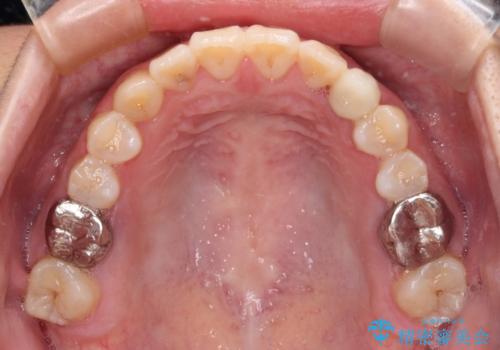

受け口で開咬を急速拡大装置とインビザラインで改善 欠損部分はインプラントにて補綴治療

矯正治療が終わるタイミングに合わせてインプラントの埋入を行っていたので、矯正治療を終了すると同時にセラミック補綴治療を行えました。

インビザラインの装着時間が不十分であったので、治療期間は長期間となりました。